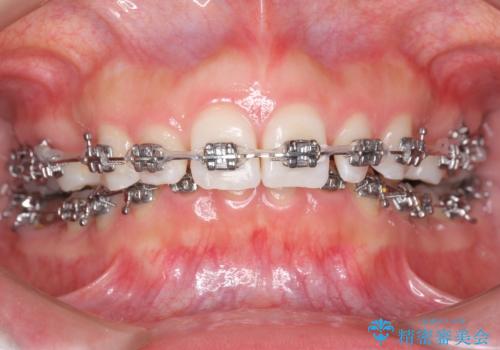

- 矯正装置

- メタル装置

- 治療期間

- 3年6ヶ月

- 出っ歯を主訴に来院。

かみ合わせが深く、治療に時間がかかりました。